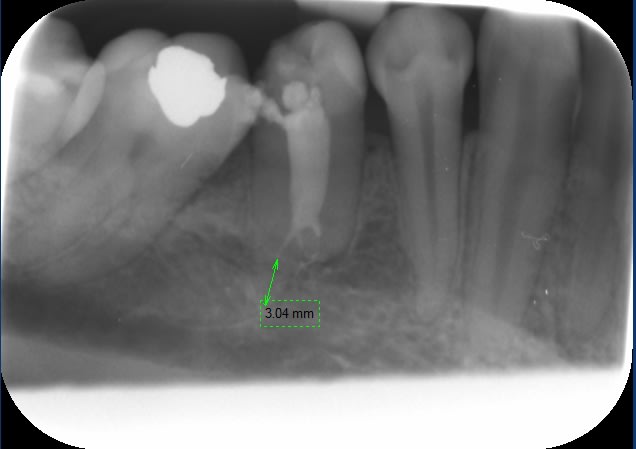

La 2è radio m'a dit arrête-toi là !

Et la 3è dont je commençais à être content avec sa forme de gastéropode, m'apprend que le canal principal n'a pas été obturé sur 2,5 mm (3-0,5 statistiques).

Conclusion double :

Nos canaux même unitaires ont parfois de drôles de forme et si j'avais tourné mentalement de 90° cette radio de dent vue de profil je serais retourné sur l'image de sa voisine et je ne me serais pas fait avoir.

Le thermocompacteur utilisé fait de belles obturations 3D pour un investissement et un temps passé très raisonnable. Je pensais que le thermocompacteur ne suffirait pas et que j'aurais de gros manques, donc les fouloirs à chaud étaient déjà calibrés au cas où.

Radios faites avec Pspix que je viens enfin d'inaugurer!